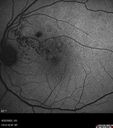

Twig (Macular) Branch Retinal Vein Occlusion with no symptoms217 views73 year old female with 20/25 vision and no symptomsJul 03, 2023